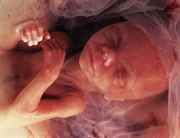

На восьмой неделе беременности плод продолжает активно развиваться, и его размеры увеличиваются. В этот период длина эмбриона составляет примерно 1,6 сантиметра, а вес — около 1 грамма. На этом этапе формируются основные органы и системы, что делает его критически важным для дальнейшего развития.

Восьмая неделя знаменуется завершением формирования основных структур, таких как сердце, которое теперь уже бьется с регулярным ритмом, и начинает функционировать. Также активно развиваются легкие, печень, почки и кишечник. Внешние признаки также становятся более выраженными: на этом этапе начинают формироваться конечности, и уже можно различить пальцы на руках и ногах.

Кожа плода еще очень тонкая и прозрачная, но уже начинается процесс формирования меланина, который отвечает за цвет кожи. На лице появляются основные черты: глаза, уши и нос начинают принимать более четкие очертания. Внутренние органы продолжают развиваться, и в этот период начинается образование половых органов, хотя пол еще нельзя определить.